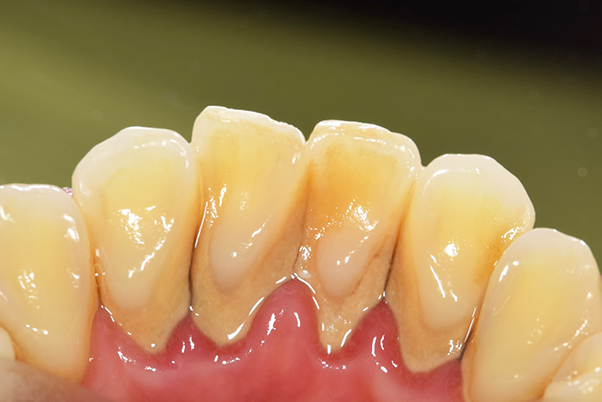

【担当医師所見】

歯周病の治療の必要性

ブラッシング方法の教授